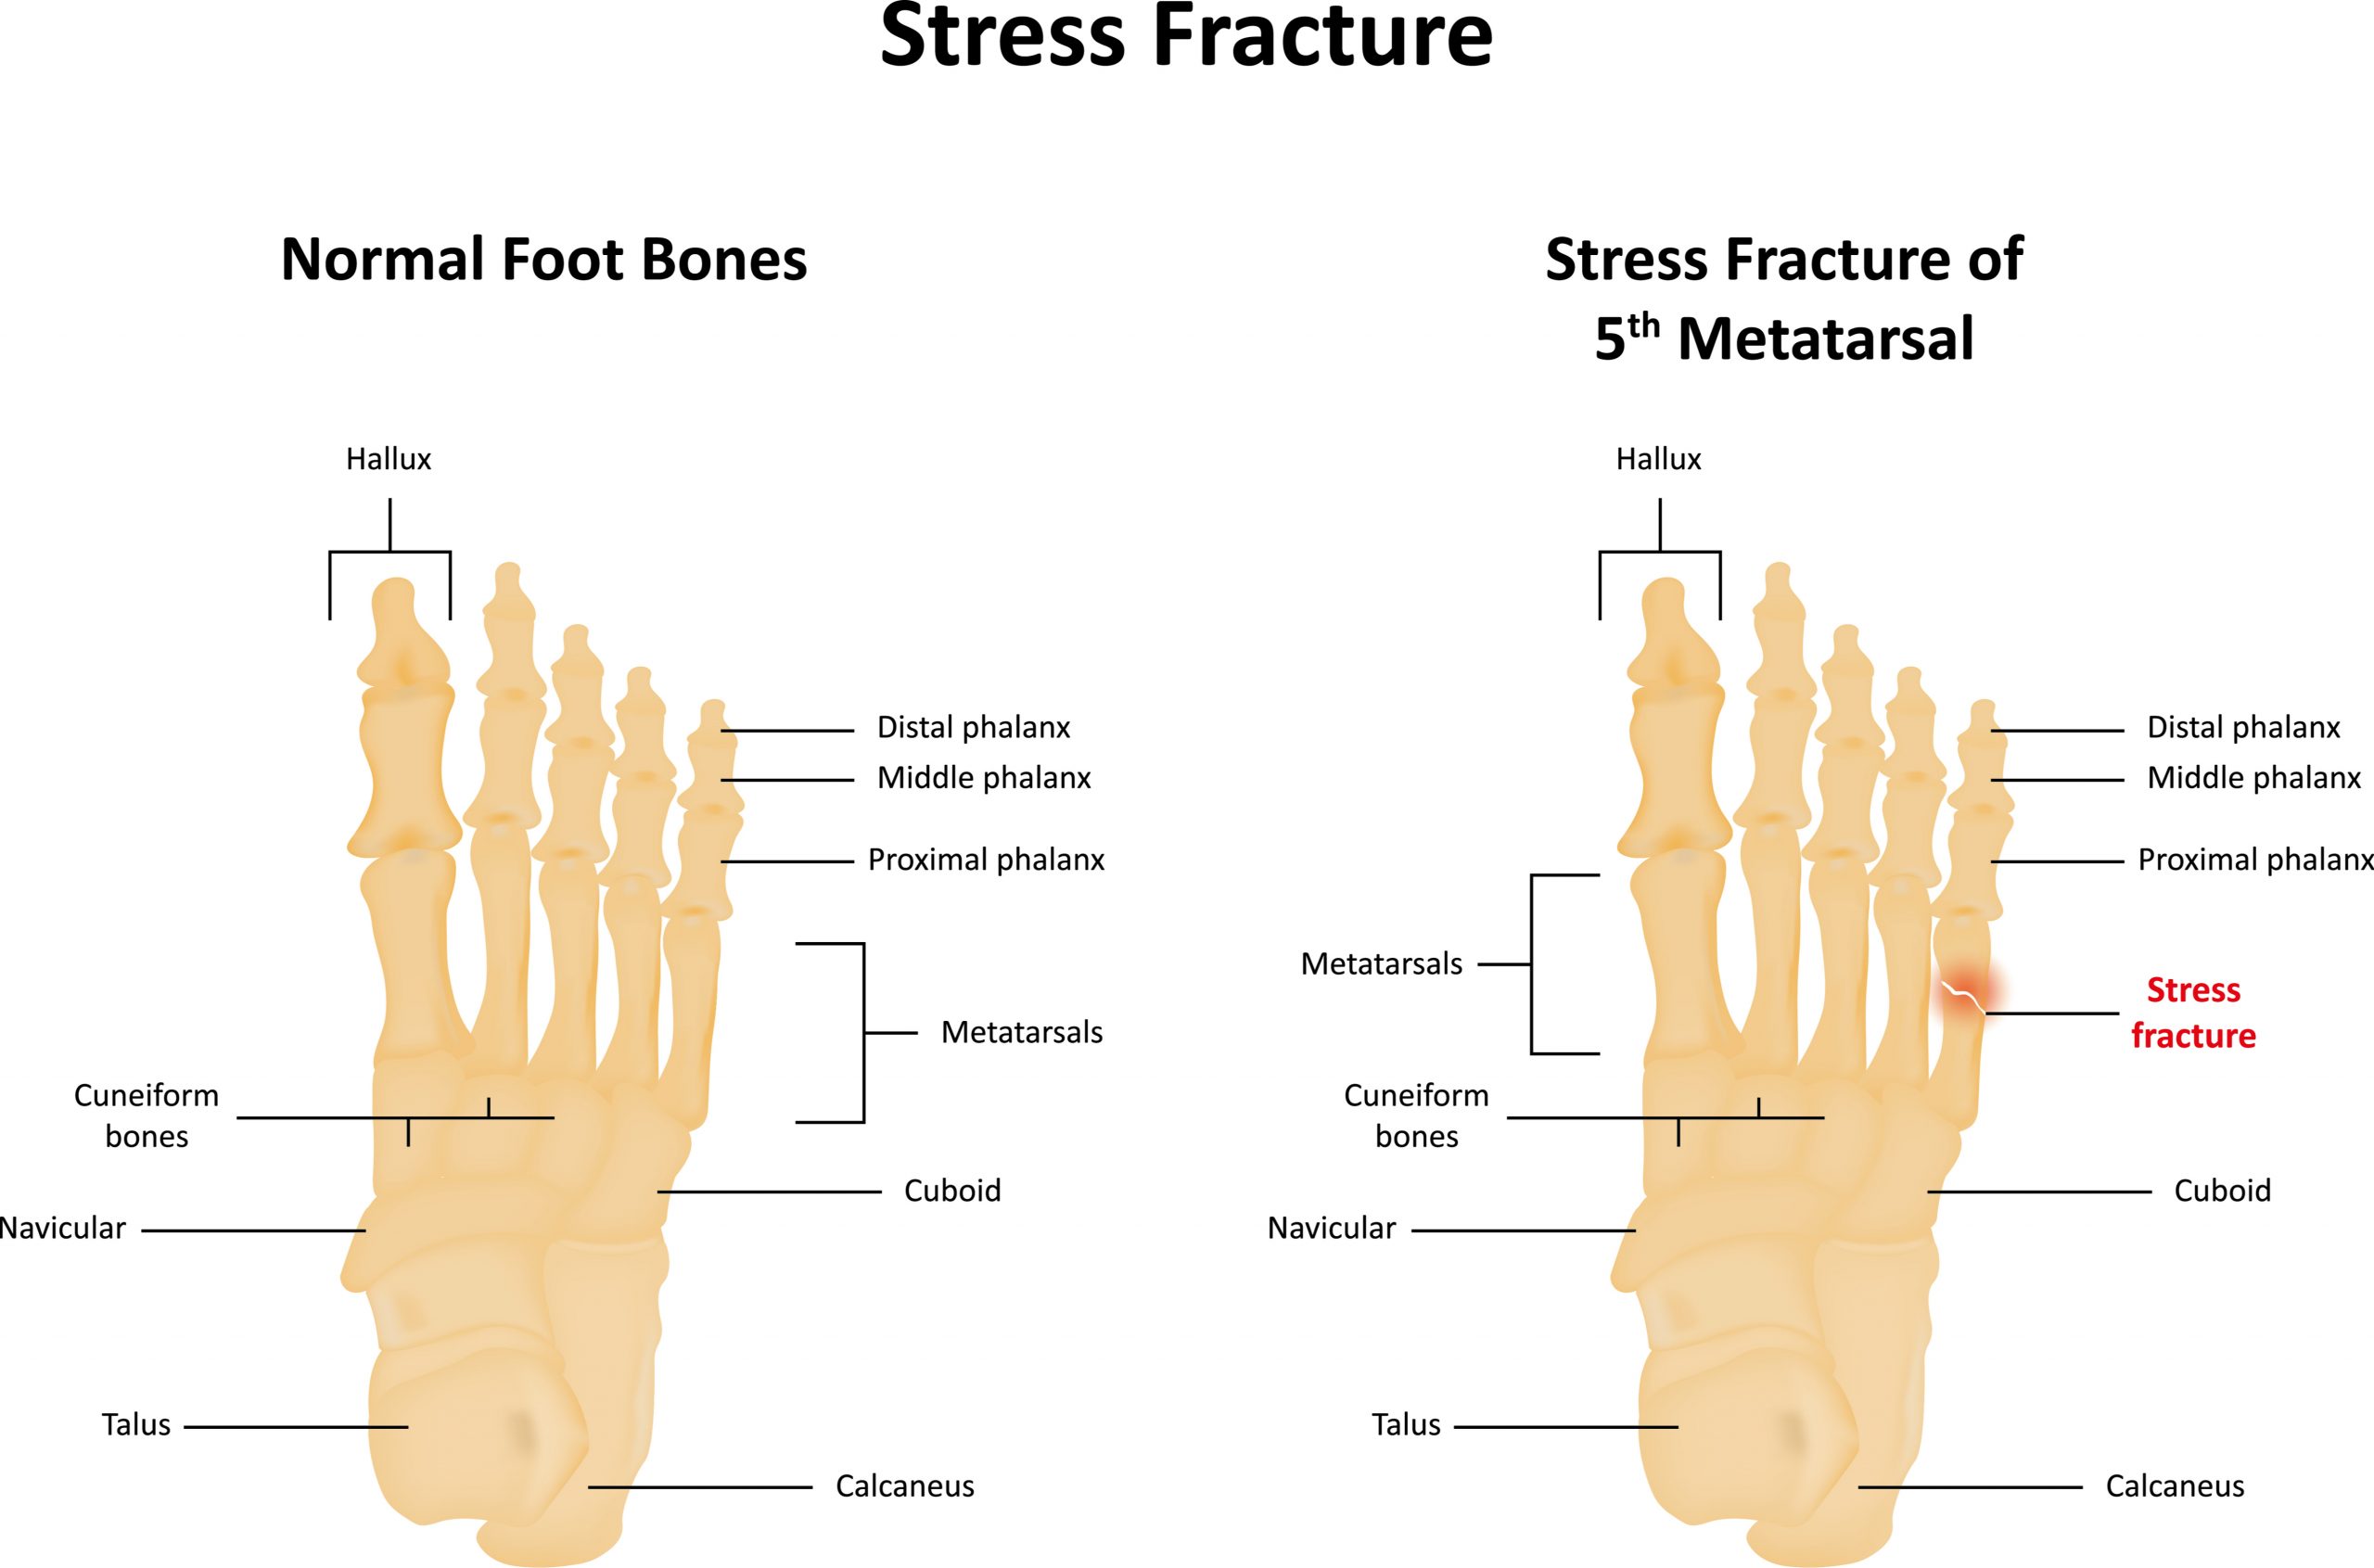

Diseases & conditions stress fractures of the foot and ankle a stress fracture is a small crack in a bone, or severe bruising within a bone. Introduction stress fractures refer to fractures occurring in the bone due to a mismatch of bone strength and chronic mechanical stress placed upon the bone. If left untreated, a stress reaction can eventually crack,.

36, 51 scintigraphy is able. Most stress fractures are caused by. One or more of the following diagnostic imaging exams may be used to confirm the presence of a foot stress fracture.

Point tenderness, swelling and changes in your. Bottom line a stress fracture of the foot is a tiny crack in one of the bones in your foot. Stress fractures are tiny cracks in a bone.